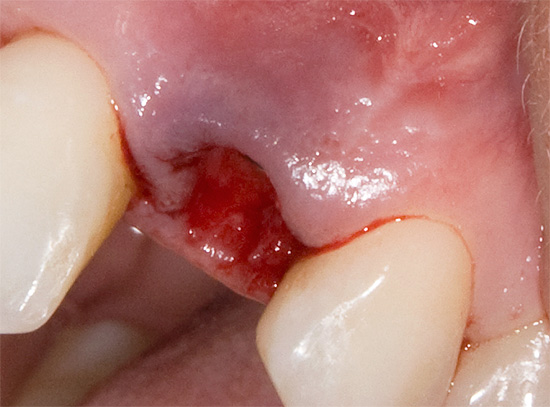

Geralmente, sob a influência de um ou mais fatores provocadores, a alveolite se desenvolve 1-3 dias após a extração do dente com uma clínica com agravamento do estado geral, mal-estar, febre, dores agudas nas gengivas, mastigação prejudicada ao lado da remoção e aparecimento de mau hálito.

Se você ignorar o desenvolvimento posterior desses sintomas alarmantes, a alveolite pode passar para o estágio nulótico purulento com a formação de osteomielite limitada da cavidade dentária. Se a temperatura de alguns dias após a extração do dente subir para 39 graus ou mais, a capacidade de trabalho cair para zero, o sono é perturbado, um odor fétido emana da boca, uma dor aguda insuportável e latejante é atormentada, e ao remover os molares inferiores (incluindo sabedoria) - a boca também se abre mal e, com um alto grau de probabilidade, a alveolite já mudou para osteomielite e é necessária a ajuda do dentista de emergência.